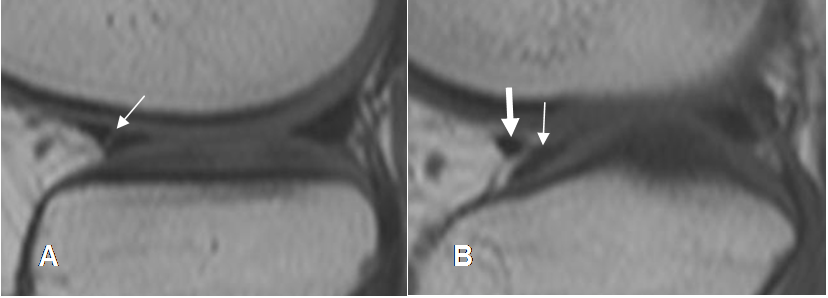

Fig 74. Ruptura meniscal oblicua.

A: RM sagital en T1 y B: RM sagital en STIR. Imagen en sentido oblicuo, que se comunica con la superficie articular inferior, por ruptura meniscal.

Fig 75. Ruptura meniscal radial.

A y B: RM sagital en T1. Alteración en la parte medial del menisco, por ruptura radial.